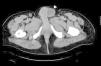

Case reportThis is a 45-year-old African American male presenting with a 2-week history of abdominal pain, anorexia, and pain during intercourse. His history was significant for an episode of severe alcohol related pancreatitis two months prior complicated with multiorgan failure and a prolonged hospitalization. There was no mention of dysuria, urethral discharge, testicular pain, history of pelvic surgery or prior similar complains in the past. Physical exam was significant for normal vital signs, and diffusely tender distended abdomen without organomegaly. A 2 x 4cm tender non-reducible mass was palpated in the left inguinal region. Pertinent laboratory results included mild leukocytosis, normal pancreatic enzymes and normal transaminases. Urine analysis was unremarkable. Abdominal CT with contrast revealed a large septated fluid collection of approximately 30cm in diameter, extending from the lesser sac to the left side of the pelvis into the left inguinal canal and scrotum. The collection was compressing against the stomach, duodenum, spleen, but there was no radiological signs of obstruction (Fig. 1). It dissected following the path of the left psoas muscle down to the pelvis (Fig. 2). At the level of the inguinal canal, it compressed against perineal structures including the base of the penis (Fig. 3). Communication of the retroperitoneal and inguinal collection was determined by visualization of the continuum through the different tomographic cuts. At all levels the collection presented with Hounsfield units ranging from five to 15, corresponding to the attenuation coefficient of cystic fluid. Percutaneous drainage was precluded due to the multiloculated nature of the pseudocyst. Considering persistence of abdominal pain and inability to advance diet, the patient underwent laparoscopic surgical drainage, and 3.5 liters of non-purulent fluid was retrieved. Seven days after the surgery, the patient presented with tachycardia, fevers, worsening abdominal pain and increased output from surgical drains. Cultures confirmed peritonitis with Pseudomona aeruginosa and methicillin resistant Staphylococcus aureus. The patient required a total of five laparotomies for debridement and retroperitoneal washout, as well as prolonged antibiotic therapy. Late complications included wound infection and incisional hernia that were later repaired. Follow up CT of the abdomen revealed a 5cm cystic lesion in the tail of the pancreas with no evidence of pelvic collections. At that time there was no further complains of dyspareunia.